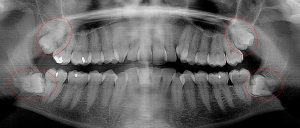

This 34 year old patient has all four third molars present (circled) and fully erupted into occlusion. They appear disease free…but are difficult to keep clean. 3rd molars are the most likely teeth to decay or have gum disease with a >98% probability that decay and gum disease will occur around all four teeth over this patient’s life time.